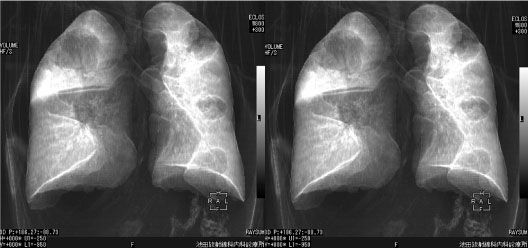

画像 2 膀胱癌からの肺転移例。Ray summation法というエックス線透視像をシミュレートした

手法で,三次元処理して平行法ステレオ像として表示した。塊状の病巣の広がりの状態や

気管支への侵襲,質の異なる病巣の広がりが示現されている。